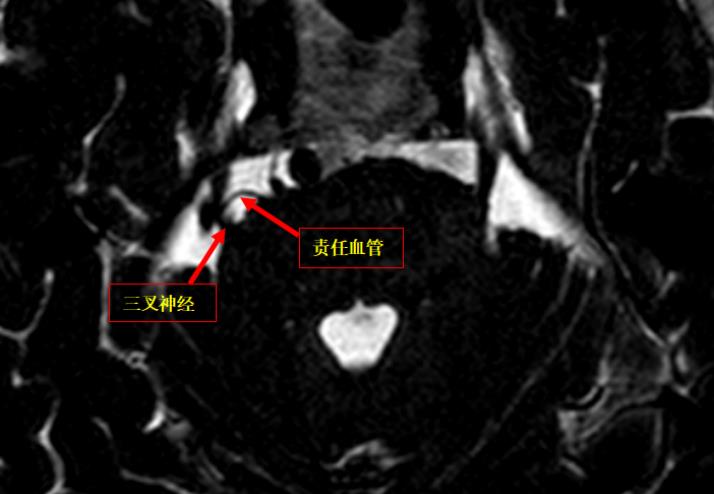

▲术前头颅MRI:右侧三叉神经经颅内段外上缘示一较粗血管影伴行,邻近并示一小血管骑跨走行,关系密切。

考虑到患者接受药物治疗无效,建议手术治疗。神经外六科团队决定在全麻下为患者实施右侧三叉神经微血管减压术。

吴杰介绍,微血管减压术是目前对于该病首选的手术方式,手术通过探查颅内三叉神经走行区,将可能的压迫血管、蛛网膜条索进行分离、松解,并用垫片将责任血管与神经根进行隔离,刺激产生根源随即消失,疼痛即可缓解,手术后效果显著,且持久。

术中,手术医生发现三叉神经上方与下方分别有一静脉与动脉压迫,这是导致患者面部疼痛的原因。医生分别将动静脉血管从神经上松解开,并用棉片垫开,解除压迫。